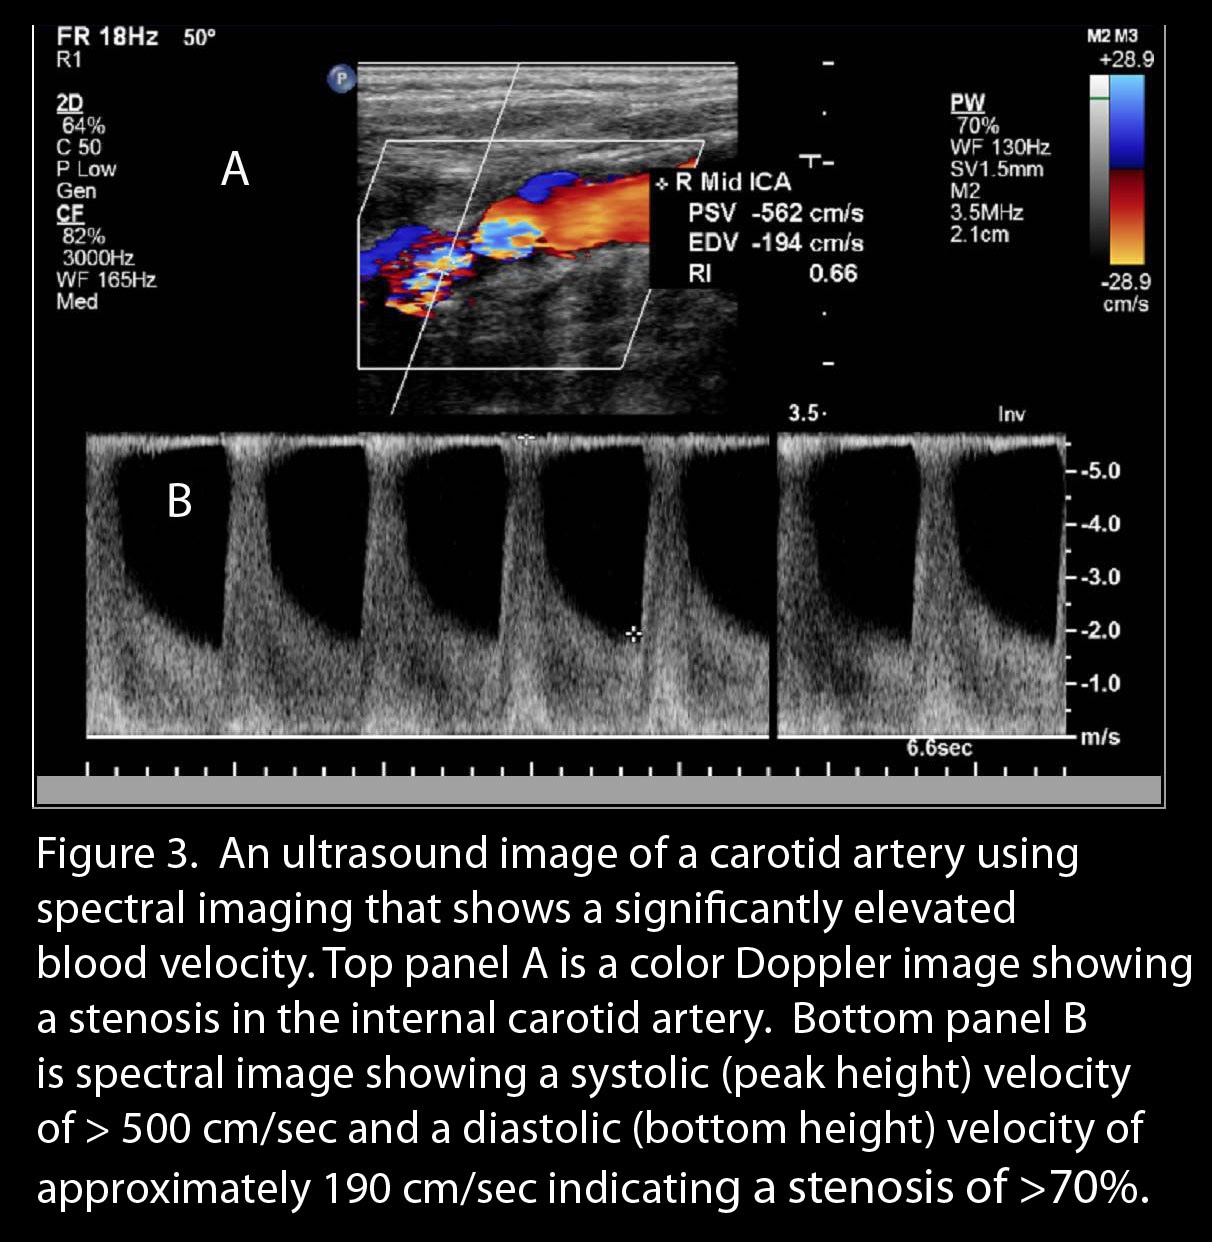

The

initial study to evaluate carotid disease is a carotid ultrasound.

This technique utilizes sound waves to view the carotid artery. A small

amount of saline gel is placed on the neck and an ultrasound probe is

used to visualize the carotid arteries (Figure 3). Ultrasound images

may reveal plaque. The amount of blockage (stenosis in medical

terminology) is determined by the velocity of blood flow through the

artery; the higher the velocity, the higher the amount of stenosis or

narrowing. One ultrasound-based technique evaluates the thickness of